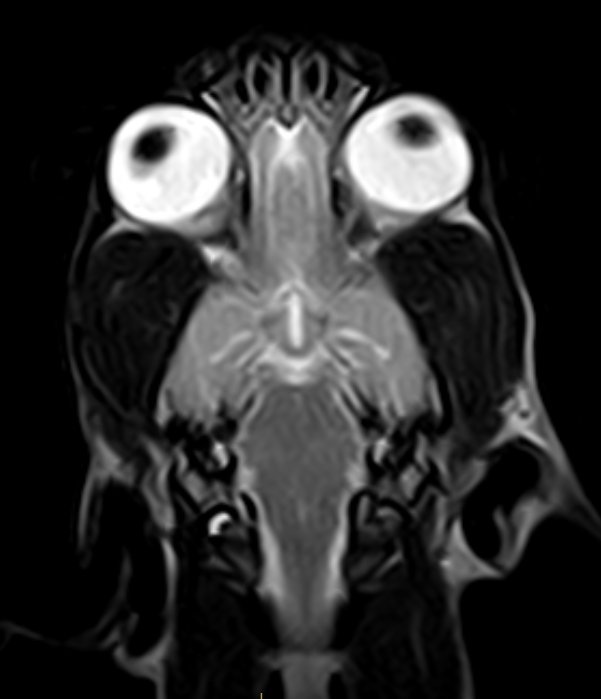

Imágenes de Calidad Premium

IMÁGENES CLÍNICAS

En la sección de imágenes clínicas, destacamos la precisión y claridad de nuestros estudios, respaldados por un equipo de radiólogos especializados en medicina veterinaria. Nos enorgullece ser un aliado confiable para veterinarios y clínicas, brindando un servicio rápido y eficiente para ayudar en la toma de decisiones clínicas fundamentadas.

Utilizamos resonancia magnética para obtener imágenes detalladas de tejidos blandos, articulaciones y el sistema nervioso central, permitiendo diagnósticos más precisos.